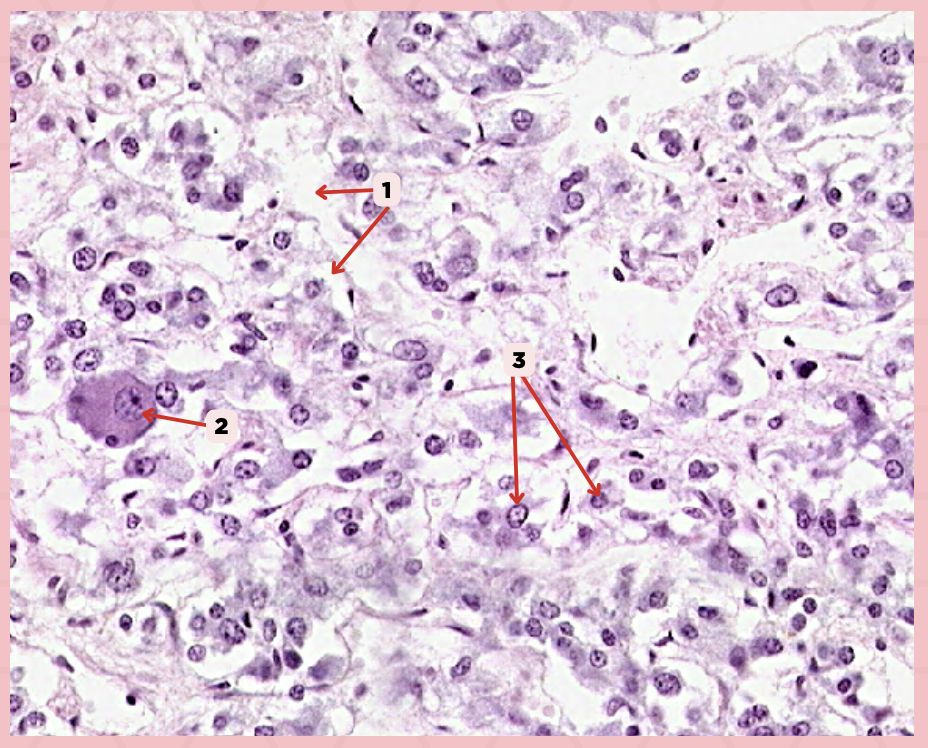

Follicular Cells

Identify the structure labeled as 1.

Colloid

Identify the structure labeled as 2.

Parafollicular Cells

Identify the structure labeled as 3.

Capillary

Identify the structure labeled as 4.